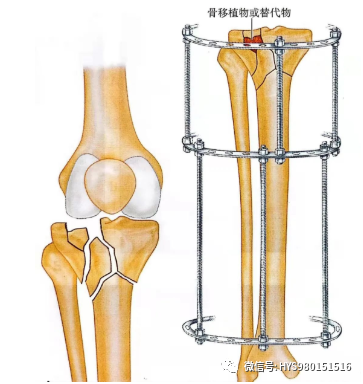

手术步骤6

• 骨缺损可以用多种方法处理:1、在切开复位内固定时使用异体或自体骨移植。2、也可以局部注射人工骨。